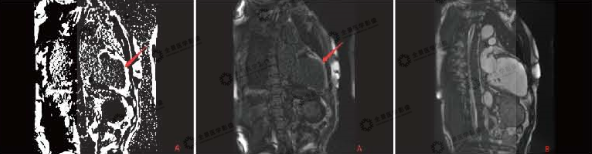

▲灌注序列

红色箭头:缺血区域充盈缺损表现

磁共振显示:该患者冠心病,心肌梗死,梗死心肌占左室总体60%,前降支供血区透壁性心肌梗死;右冠状动脉、旋支供血区基底部及中间段大部分心肌存活,心尖段心肌透壁性梗死。全心增大,心功能不全。